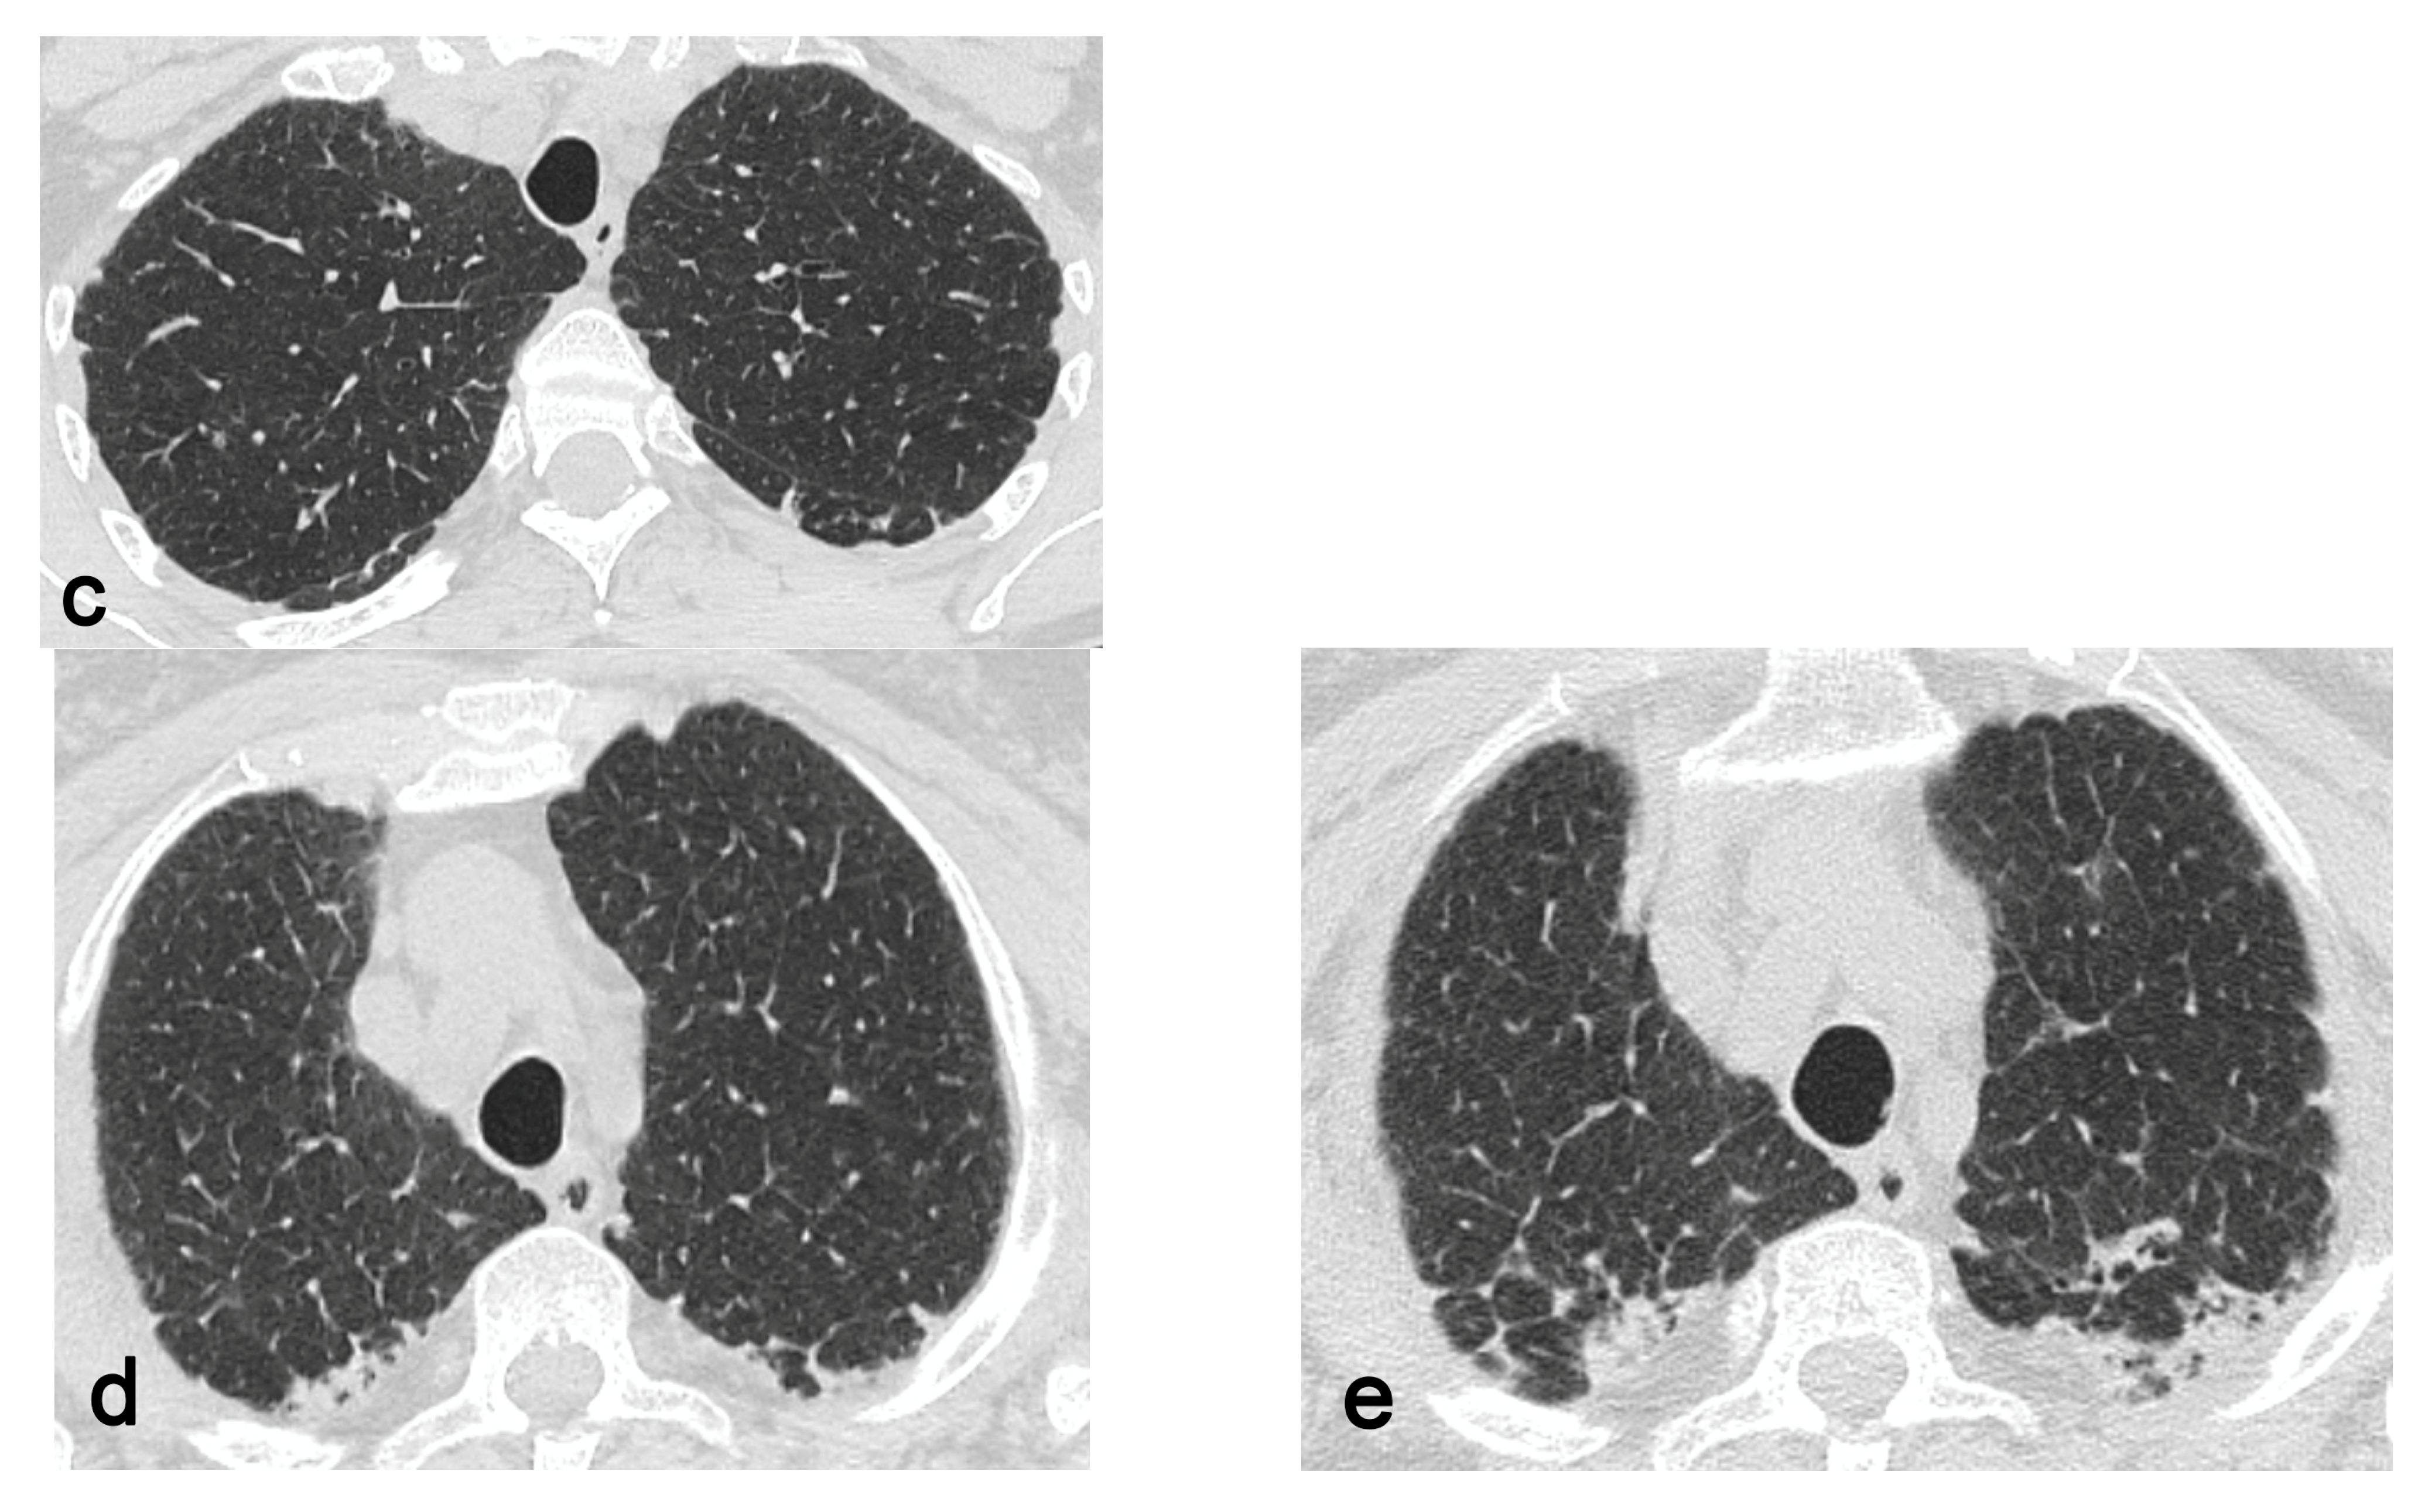

In 87 out of 106 patients without progressive disease, apart the involvement of the apical and or dorsal segments of the upper lobes, 39 exhibited an involvement of the apical segment of the RLL, 53 saw an involvement of the right fissure, 15 saw an involvement of the ventral segment of the RUL, 30 saw an involvement of the apical segment of the LLL, 52 saw an involvement of the left fissure, and 12 saw an involvement of the ventral segment of the LUL. On the other hand, regarding the 19 patients with an increased score between the first and the second exam, 17 exhibited an involvement of the apical segments of the lower lobes and fissures bilaterally, while 14 exhibited an involvement of the ventral segments of the superior lobes. Statistical analysis revealed a significant difference between the two groups (progressive vs. non-progressive disease) regarding the involvement of the ventral segments of the upper lobes (p = 8.09 × 10−7 and p = 5.71 × 10−8 for the RUL and the LUL, respectively), fissures (p = 0.02 and p = 0.01 for the right and left fissures, respectively) and apical segments of the lower lobes (p = 1.67 × 10−5 and p = 0.01 for the LLL and RLL, respectively), as shown in Table 2. Among these 19 patients exhibiting a worsening of PPFE-like alterations, 5 showed an associated fibrotic pattern that was “UIP consistent”, 1 of whom worked in a knitwear factory and 1 of whom was exposed to paints. In total, 4 patients showed only PPFE-like lesions, 1 of whom was affected by psoriatic arthritis, 1 who was exposed to asbestos and 2 who were affected by mixed connective tissue disease. In total, 3 patients showed bronchiectasis with infective chronic bronchiolitis, 2 of whom were detected as being positive at BAL for atypical mycobacteria (Figure 2). In total, 2 patients were affected by chronic extrinsic allergic alveolitis, one of whom was a hairdresser and the other a breeder of canaries. Two patients showed a concomitant emphysema.

Figure 2. Bronchiectasis (arrows in (a)) and infective bronchiolitis (arrowheads in (b)) in a 67-year-old woman affected by atypical mycobacteriosis and PPFE-like lesions, which involve upper segments of lower lobes, fissures and apico-dorsal portions of upper lobes (c,d). A follow-up exam after three years (e) shows a progression of PPFE-like lesions.